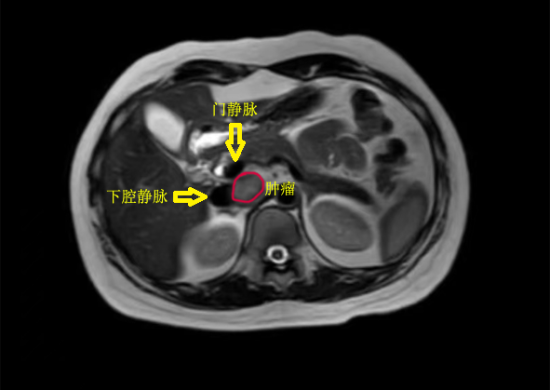

经过周密准备,团队决定采用机器人手术系统为患者实施微创手术。机器人手术系统具有放大的三维立体视野和7个自由度的仿真手腕器械,能够在狭小空间内完成精细操作,特别适合此类复杂解剖部位的手术。术中发现,肿瘤位于下腔静脉后方,与门静脉、左肾静脉及腹主动脉关系极为密切,稍有偏差就可能引发致命性大出血。在陈之显主任医师精准操控下,机器人机械臂灵活地在血管间隙中游走,一步步精细分离,完整保留了重要血管。